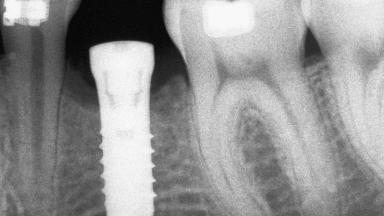

Autologous Block Graft and Guided Bone Regeneration (GBR) for Horizontal Ridge Augmentation in the Posterior Mandible

An 18-year-old man was referred for implant therapy in the posterior mandible to the Department of Oral Surgery and Stomatology (University of Bern, Switzerland). He was healthy and did not smoke. Tooth 35 was congenitally missing, involving a single-tooth edentulous space that offered an adequate mesiodistal dimension for implant placement but exhibited a typical pattern of buccal flattening. A panoramic radiograph was obtained, which revealed a sufficient vertical bone height above the mandibular canal and a normal bone structure in the edentulous area.

# of Implants 1

Type of Implants One-Piece

Bone Volume Deficient horizontally, requiring prior grafting